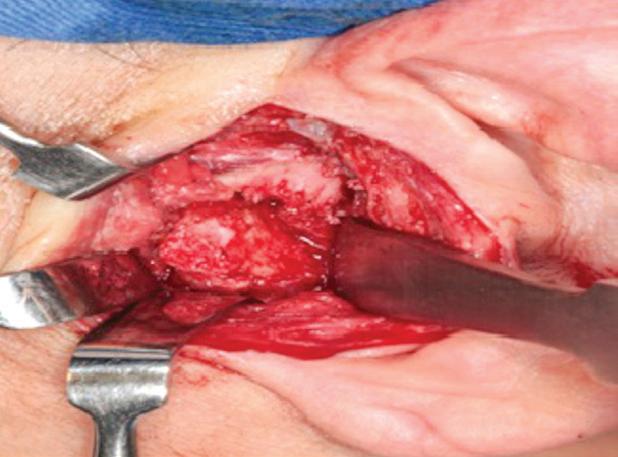

A paciente foi submetida à reconstrução total bilateral com próteses de estoque do sistema Biomet (Biomet 3i do Brasil Ltda., São Paulo/SP, Brasil). Foram realizados, bilateralmente, acessos pré-auricular e retromandibular, condilectomia e, por fim, instalação das próteses de estoque. A sequência da instalação das próteses consistiu em primeiro o componente fossa e, depois, o componente mandibular (Fig. 2). O paciente encontra-se aos cinco anos de pós-operatório, com uma boa abertura de boca e oclusão preservada e sem dor (Fig. 3).

Figura 2: A) Acesso pré-auricular direito. B) Acesso pré-auricular esquerdo. C) Componente mandibular direito instalado na face lateral do ramo da mandíbula através do acesso retromandibular. D) Componente fossa direito instalado na base do crânio através do acesso pré-auricular. E) Componente mandibular esquerdo instalado na face lateral do ramo da mandíbula através do acesso retromandibular. F) Componente fossa esquerdo instalado na base do crânio através do acesso pré-auricular.